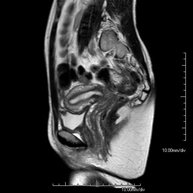

Prova diagnòstica no invasiva que consisteix en l'obtenció d'imatges d'alta definició anatòmica de la pelvis mitjançant l'ús d'un camp electromagnètic i ones de ràdio (amb un emissor i un receptor). No utilitza radiació ionitzant. Es realitza per a l'estudi de patologies d'úter, d'ovari, de trompes i de vagina, ja siguin d'origen tumoral, inflamatori o vascular. També permet valorar les estructures adjacents localitzades a la pelvis i la identificació de les seves alteracions. De vegades és necessari l'ús de contrast intravenós (Gadolini) per caracteritzar les lesions. - RM Pelvis masculina